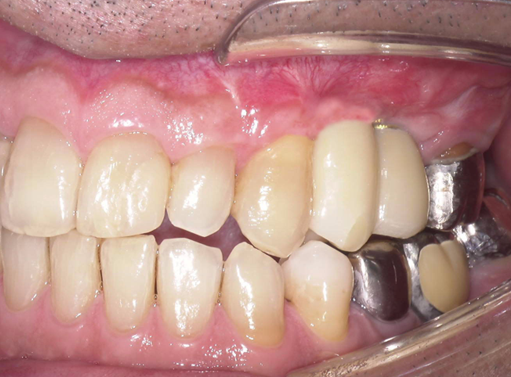

予定通りジルコニアクラウンにて、インプラント修復が行えました。